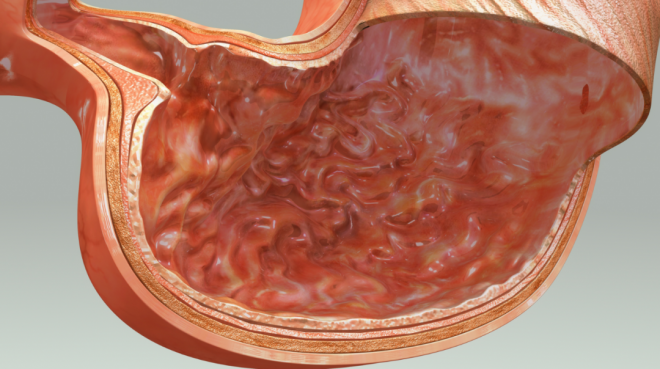

看看胃是個什麼東西

胃長得像一個大蠶豆,上通賁門連接食管,下通幽門連接十二指腸。

在牙齒咀嚼下,被初步消化的食物會通過食道來到胃的前門。

接收到來自食物的敲門信號后,胃會立即敞開大門

讓食物掉進包含胃酸、胃蛋白酶原、粘液和內因子的胃液里,然後殺死食物中的大部分細菌。

緊接著胃會以每分鐘3次的頻率進行肌肉收縮,使食物與液體充分混合,把塊狀食物變成粘稠周狀的食糜。

最後按照時間批次一點一點地把食物「塞進」幽門,進入腸道,進行更深一步的消化。